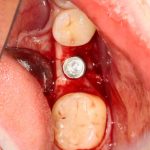

Рекомендации по установке имплантов. Для всех. Часть V.